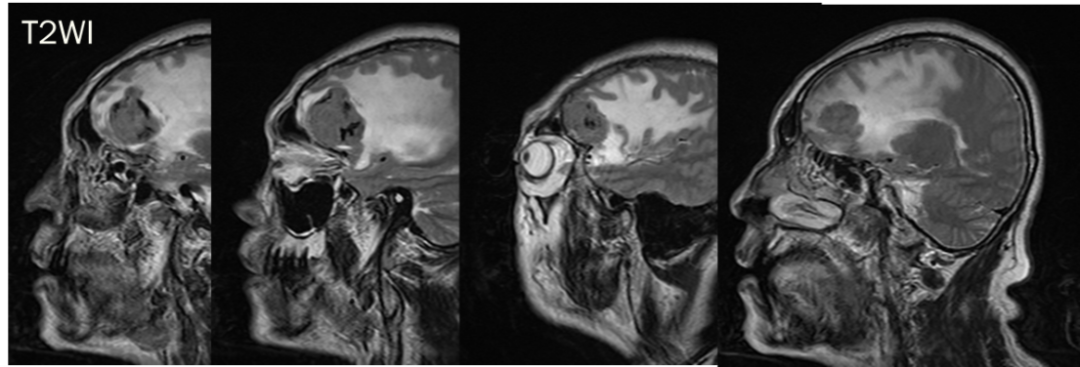

CASE 4

男,62 岁

右侧顶叶区混杂信号占位,T1、T2 内部条样低信号影,血管留空信号;增强可见明显强化,内部信号欠均匀,内见强化迂曲血管影。

诊断:右侧顶叶区血管外皮瘤